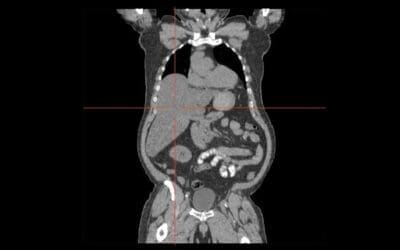

Liver and Causes of Hepatomegaly

Hepatomegaly means an enlarged liver, often a sign of underlying conditions like hepatitis, fatty liver, or heart failure. Diagnosis involves physical exams and imaging.